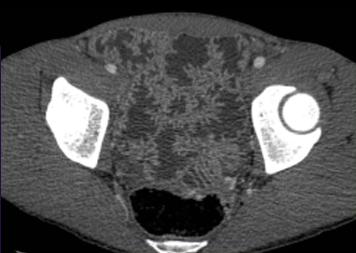

| Image fibrose sclerosant

lipomatose de ilein avec epaissisement marque de sa

paroi. Maladie de Crohn de ileon en coupe TDM axiale

|